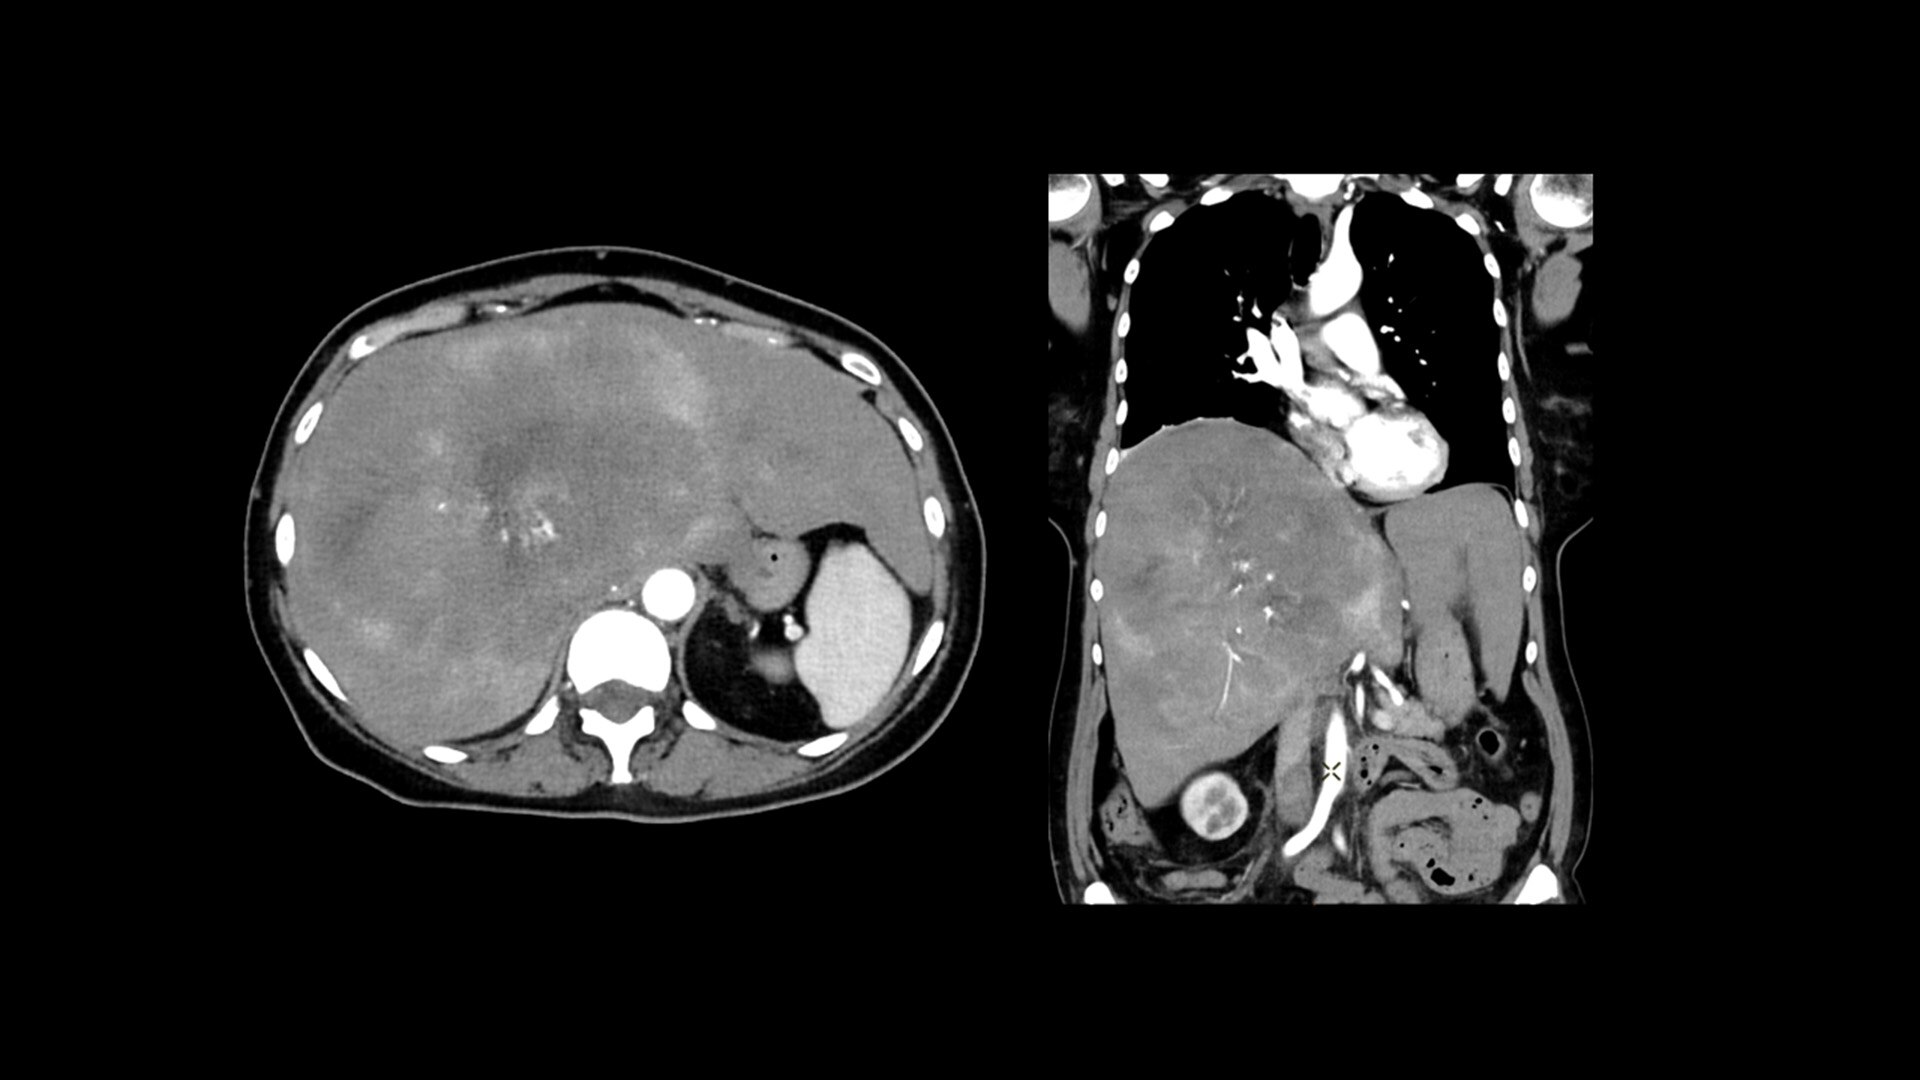

Cardiac CT has become a front-line, non-invasive imaging tool for diagnosing, treatment planning and monitoring of cardiovascular disease

Healthcare providers are striving to improve patient health but are struggling with increasingly complex exams, insufficient or inexperienced staff, and operational and capital efficiency. Revolution™ Vibe, designed to deliver leading-edge technology, features advanced cardiovascular capability. It improves patient access and operational efficiency, prioritizes patient care and supports your facility's growth with lower lifecycle costs.

Unlimited 1-Beat Cardiac is designed to provide consistent, high-quality imaging for accurate diagnoses, even in challenging patients with atrial fibrillation, breath-holding difficulties, heavily calcified coronaries, in-stent restenosis, and situations where an ECG trace is unavailable.